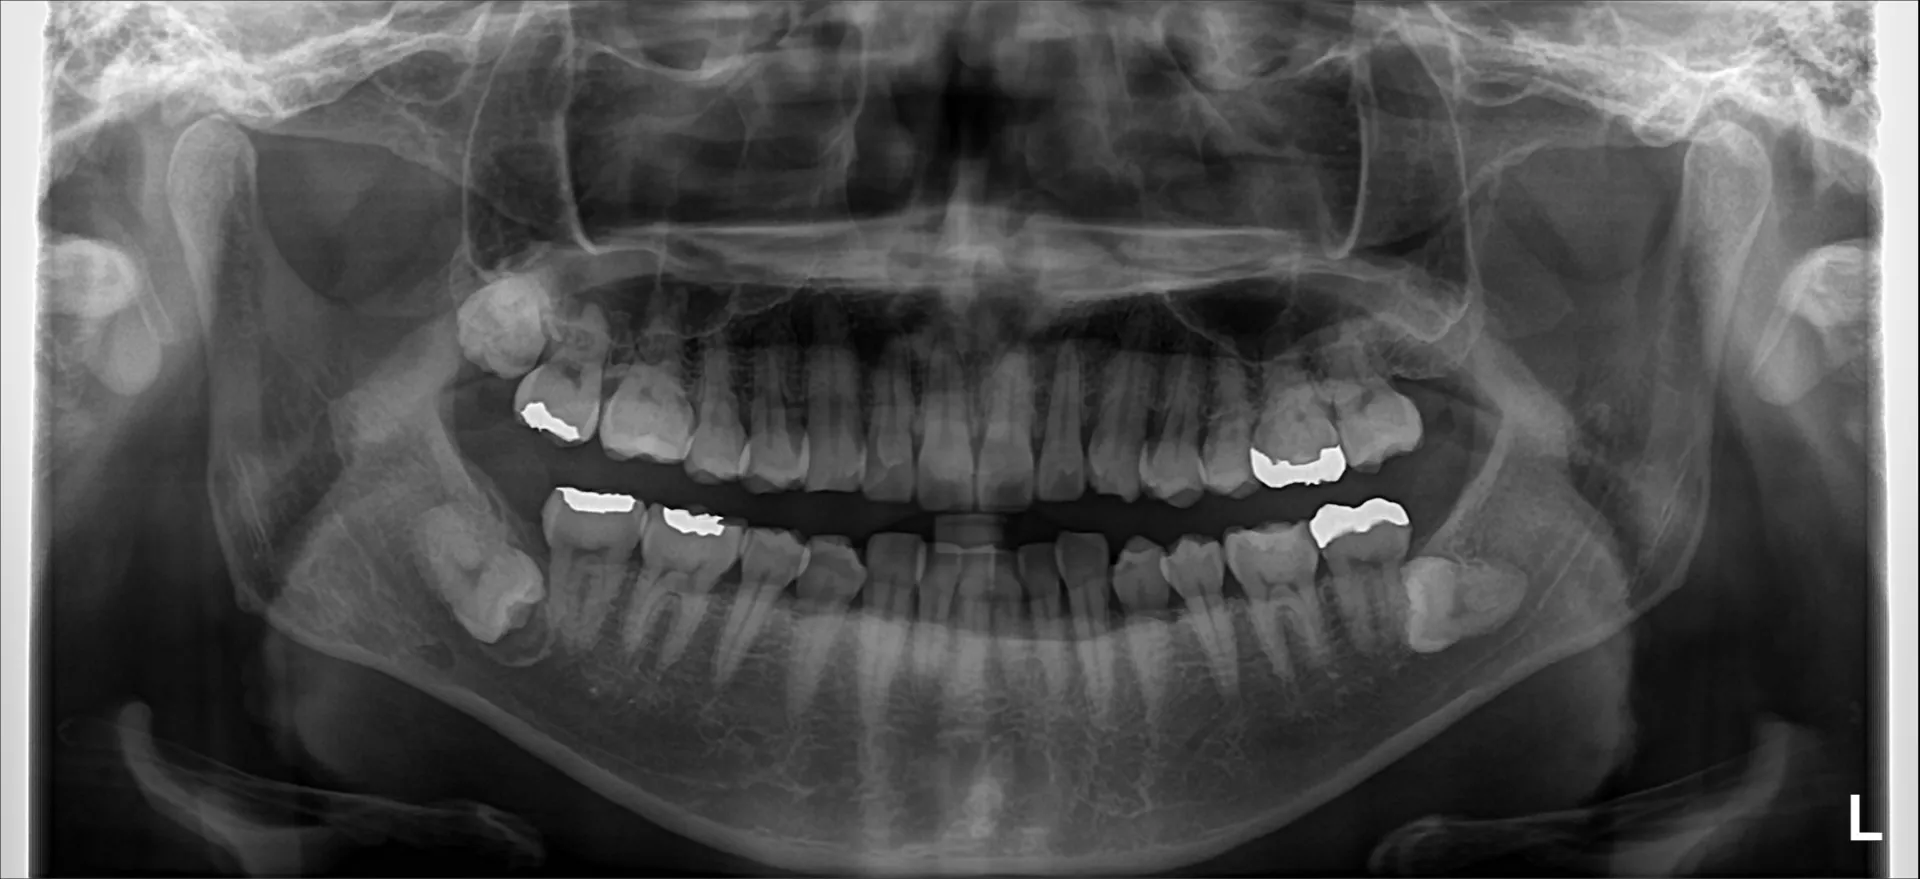

まず親知らずのレントゲン写真を2つお見せします。

どちらも横向きに生えた親知らずですが、抜歯の難易度は大きく異なります。

難易度ではレントゲン写真1>レントゲン写真2となります。

・横向きであることは同じですが、角度は大きく違います。

写真1は下に向かっている。写真2は上に向かっている。

抜歯は口腔内から治療を行うために、上に向いている方が器具が届きやすく、目で見える範囲で治療を行うことができます。

・骨に埋まっている範囲は写真1>写真2。

骨に埋まっている範囲が大きければ大きいほど骨を切削して掘り出す必要が出てきます。

周りの骨を削合すれは当然創傷は大きくなり、腫れや出血、痛みなどの症状も出やすくなります。

・下顎管(神経や血管のある管)との距離や歯の接している範囲

下顎管の損傷は神経麻痺のリスクや大量出血のリスクが大きくともなってきます。

近ければ近いほど、範囲が多ければ多いほど慎重に治療を行う必要があるために抜歯時間も長くなる傾向にあります。

・歯根の開き方

歯根は写真1は単根と言って1つにまとまっています。しかし写真2では2根にはっきりと分かれていてカニの爪のように彎曲もしています。

この場合は写真2の方が難易度は上がってきます。